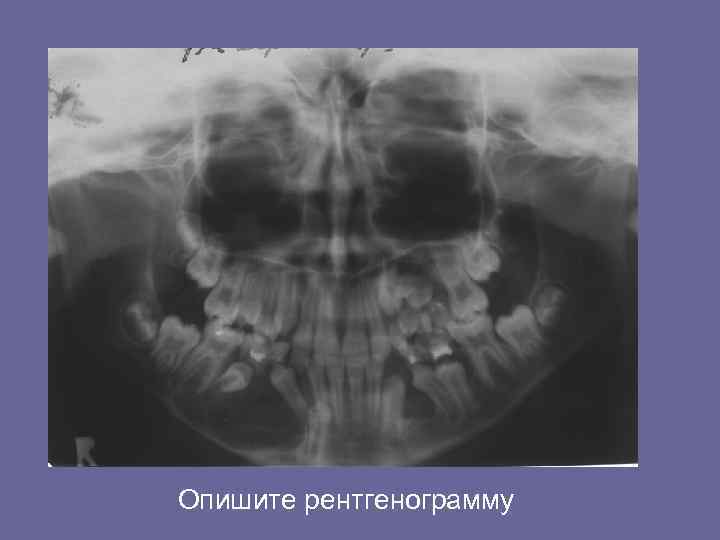

Взаимоотношение кист с зачатками постоянных зубов. Опишите рентгенограмму.

Опишите рентгенограмму